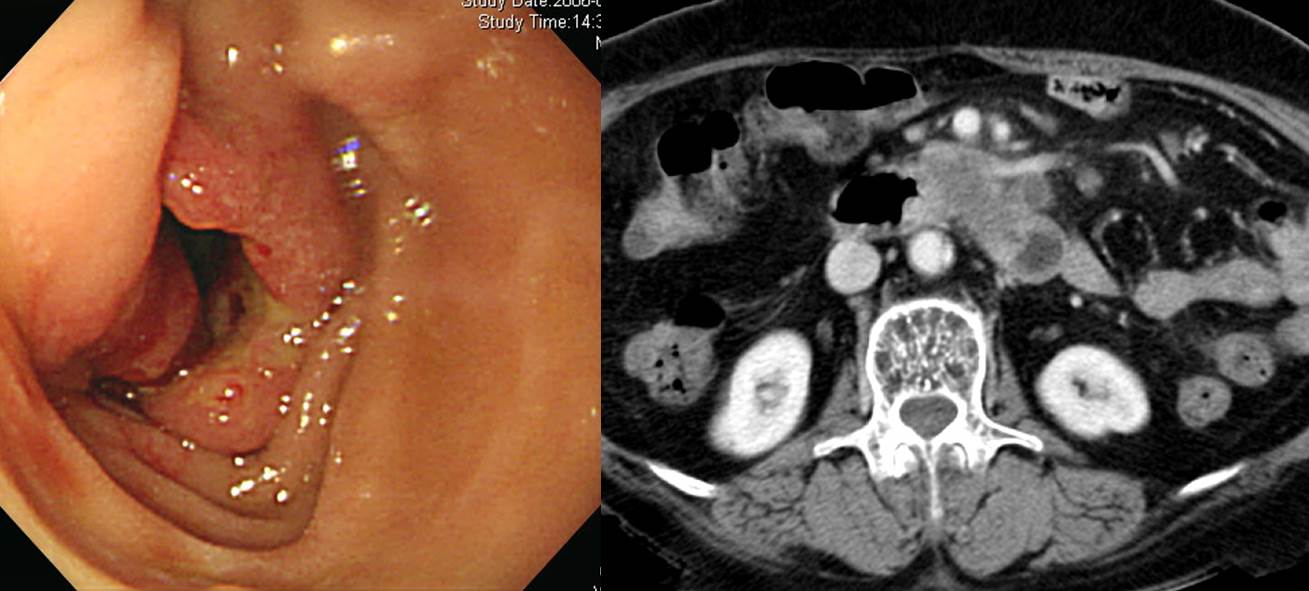

55 years old woman visited the health screening center due to abdominal pain for a few weeks. A duodenal lesion was found and referred. What is your impression?

Immediately after referral, endoscopic examination was done.

The pathology was adenocarcinoma (M/D). However, there were multiple hepatic metastatis.

When I review the initial endoscopy and second endoscopic images, it looks like an acute benign duodenal ulcer with severe edematous change. Is there a clue suggessting cancer? It is very difficult. Compared the small ulcer crator, the mucosal edema is too severe. Benign ulcer symptoms usually disappear very quickly with medication. Considering the prominent edema and persistent symptom after medication may be important for the correct diagnosis. Biopsies are necessary for initial severe duodenal ulcer to rule out malignancy.